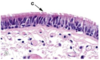

Respiratory epithelium

c = cilia

has goblet cells

Pseudostratified columnar ciliated

Respiratory epithelium

BM - basement membrane

C - cilia

G - goblet